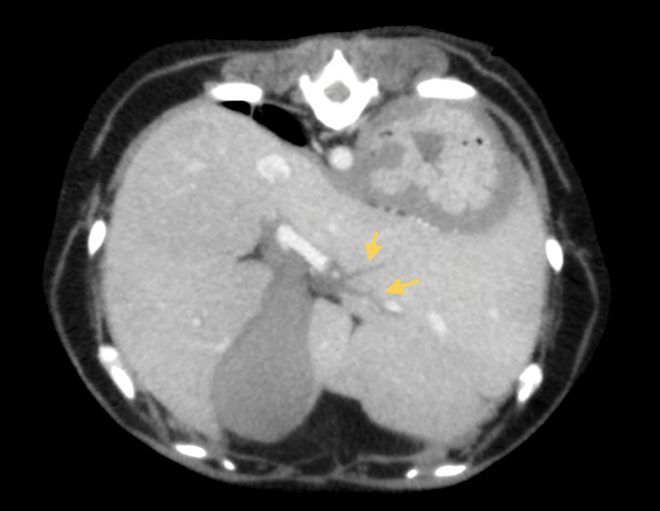

頻回の嘔吐と食欲不振を訴えて病院に来られたワンちゃん、血液検査で肝酵素と炎症マーカーの重度上昇があり、以前から胆嚢粘液嚢腫を抱えていたため、破裂などを疑わせる状況でした。超音波検査とCT検査では、胆嚢周囲の炎症、総胆管と肝内胆管の肥厚が見られましたが、破裂や閉塞所見は認めませんでした。胆嚢破裂や閉塞がない状態で、このような劇的な症状が起きることは比較的珍しいと思います。しかし、胆嚢粘液嚢腫が病態に関与していることは間違いなかったため、飼い主様に同意してもらい、その日のうちに胆嚢摘出術を行いました。

↑総胆管壁の肥厚